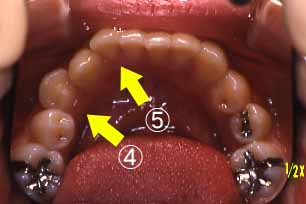

上顎

(ミラー像)

C右下4番目の歯がひっかか

っている。

D右下2番目の歯が外へ出て

いる。